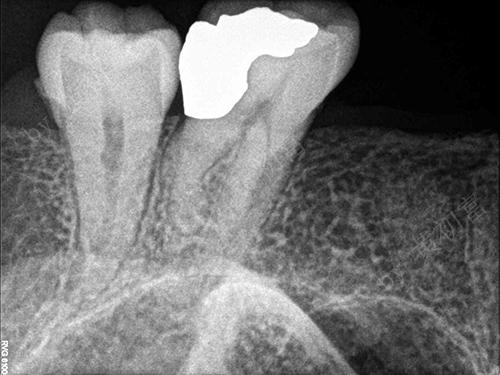

急性牙髓炎案例(一)

性别:女

年龄:59

主治医生:王琳勇

所在门诊:宁德中富口腔

主诉:左侧后牙遇冷热刺激剧痛3天

治疗方案:26根管治疗后数值天聪

术后